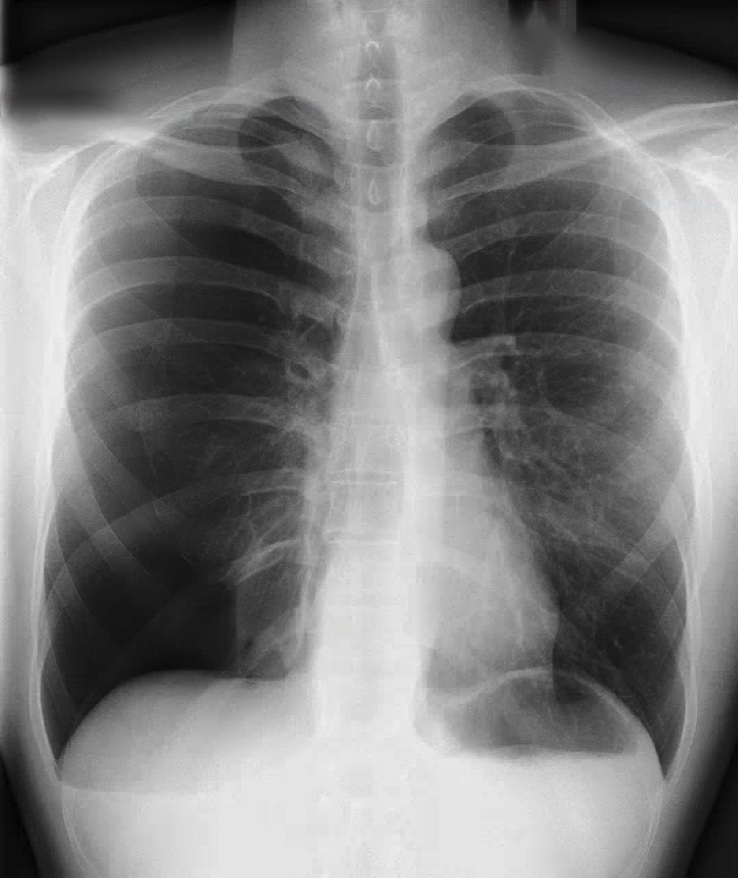

What’s the Diagnosis? Gepost op 25 maart 201825 maart 2018 door netwerkvsseh What’s the Diagnosis? @emdaily.cooperhealth.org Dit delen: Delen op X (Opent in een nieuw venster) X Share op Facebook (Opent in een nieuw venster) Facebook Delen op LinkedIn (Opent in een nieuw venster) LinkedIn E-mail een link naar een vriend (Opent in een nieuw venster) E-mail Afdrukken (Opent in een nieuw venster) Print Vind-ik-leuk Aan het laden... Gerelateerd